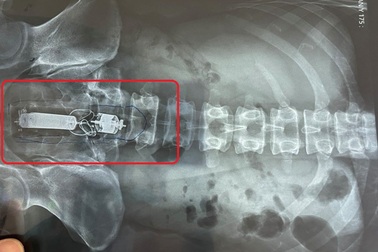

Sextoy kẹt trong trực tràng người đàn ông khi đang "tự sướng"Đang "tự sướng" thì dương vật giả lọt vào trực tràng khiến người đàn ông phải nhập viện cấp cứu. Sau nỗ lực thủ thuật các bác sĩ đã lấy được sextoy ra ngoài giúp bệnh nhân tránh cuộc mổ lớn.